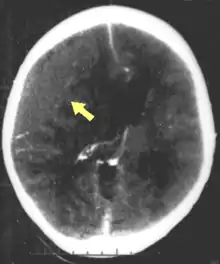

One type of focal injury, cerebral laceration, occurs when the tissue is cut or torn.[37] Such tearing is common in orbitofrontal cortex in particular, because of bony protrusions on the interior skull ridge above the eyes.[31] In a similar injury, cerebral contusion (bruising of brain tissue), blood is mixed among tissue.[23] In contrast, intracranial hemorrhage involves bleeding that is not mixed with tissue.[37]

Hematomas, also focal lesions, are collections of blood in or around the brain that can result from hemorrhage.[11] Intracerebral hemorrhage, with bleeding in the brain tissue itself, is an intra-axial lesion. Extra-axial lesions include epidural hematoma, subdural hematoma, subarachnoid hemorrhage, and intraventricular hemorrhage.[38] Epidural hematoma involves bleeding into the area between the skull and the dura mater, the outermost of the three membranes surrounding the brain.[11] In subdural hematoma, bleeding occurs between the dura and the arachnoid mater.[23] Subarachnoid hemorrhage involves bleeding into the space between the arachnoid membrane and the pia mater.[23] Intraventricular hemorrhage occurs when there is bleeding in the ventricles.[38]

Movement disorders that may develop after TBI include tremor, ataxia (uncoordinated muscle movements), spasticity (muscle contractions are overactive), myoclonus (shock-like contractions of muscles), and loss of movement range and control (in particular with a loss of movement repertoire).[89][147] The risk of post-traumatic seizures increases with severity of trauma (image at right) and is particularly elevated with certain types of brain trauma such as cerebral contusions or hematomas.[138] People with early seizures, those occurring within a week of injury, have an increased risk of post-traumatic epilepsy (recurrent seizures occurring more than a week after the initial trauma).[148] People may lose or experience altered vision, hearing, or smell.[11]